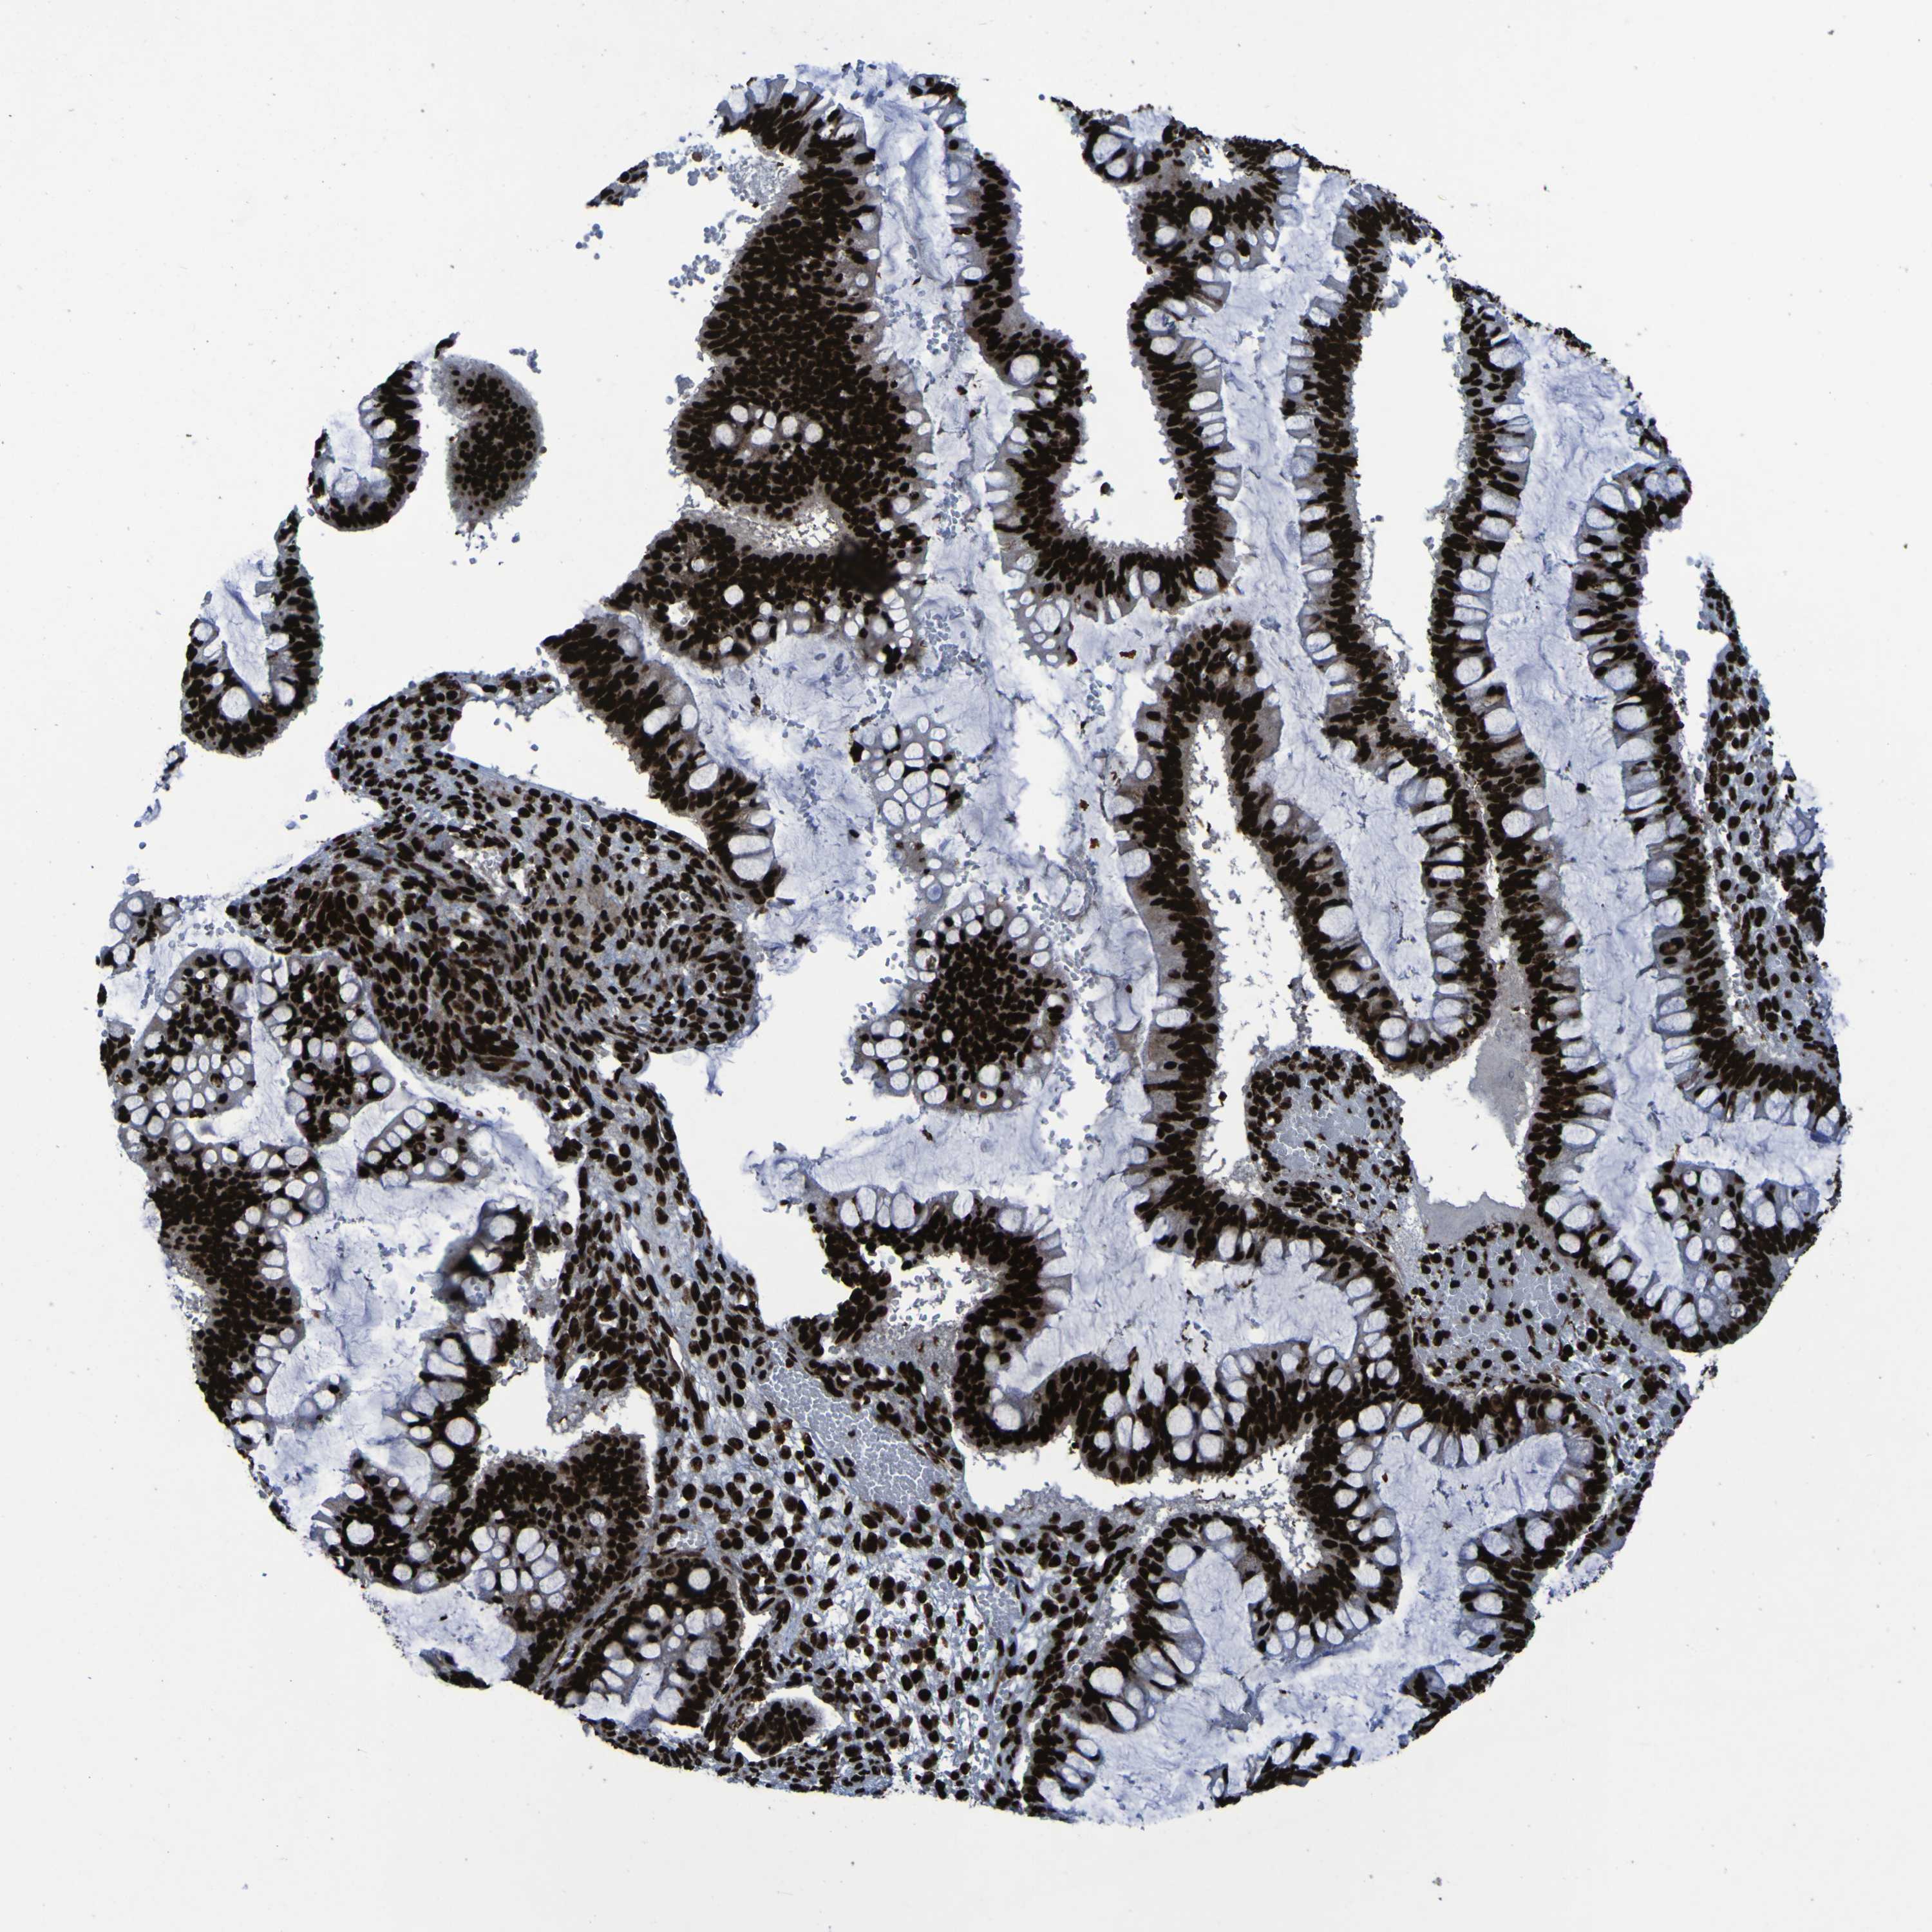

OVARIAN CANCER - Protein expressioni

A mouse-over function shows sample information and annotation data. Click on an image to view it in a full screen mode. Samples can be filtered based on level of antibody staining by selecting one or several of the following categories: high, medium, low and not detected. The assay and annotation is described here.

Note that samples used for immunohistochemistry by the Human Protein Atlas do not correspond to samples in the TCGA dataset.

Antibody stainingi

Antibody staining in the annotated cell types in the current human tissue is reported as not detected, low, medium, or high, based on conventional immunohistochemistry profiling in selected tissues. This score is based on the combination of the staining intensity and fraction of stained cells.

Each image is clickable and will lead to virtual microscopy that enables deeper exploration of all samples and also displays staining intensity scores, fraction scores and subcellular localization as well as patient and tissue information for each sample.

Antibody CAB012983

Staining

High

Medium

Low

Not detected

Intensity

Strong

Moderate

Weak

Negative

Quantity

>75%

75%-25%

<25%

None

Location

Nuclear

Cytoplasmic/membranous

Cytoplasmic/membranous,nuclear

Cystadenocarcinoma, serous, NOS

Carcinoma, endometroid

Cystadenocarcinoma, mucinous, NOS

Carcinoma, NOS